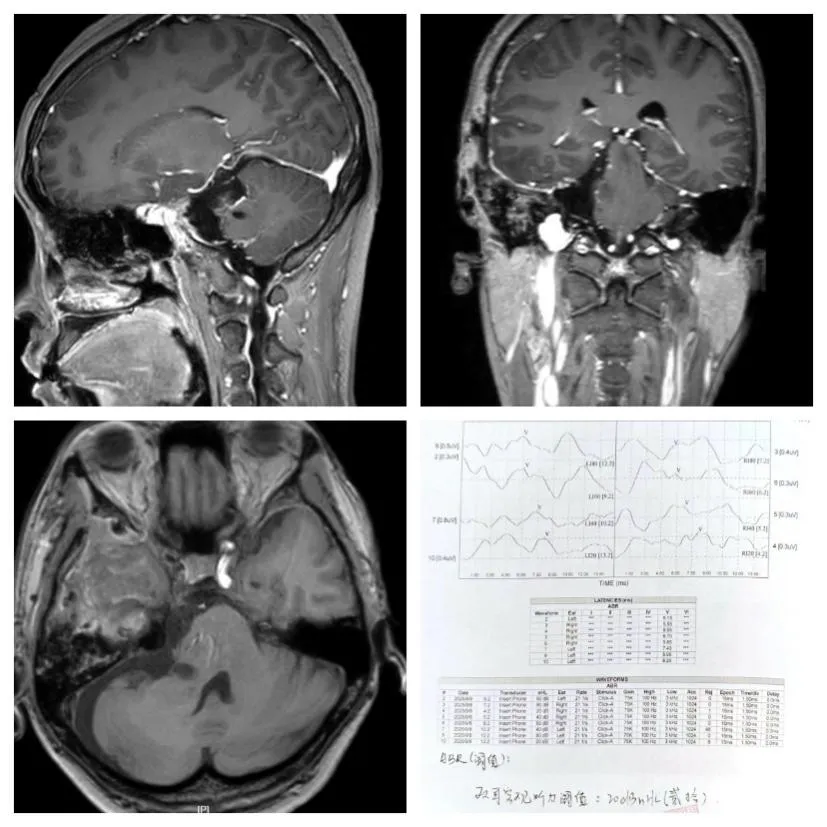

手术取得了圆满成功!术后核磁共振复查结果显示:肿瘤被全部切除,毫无残留迹象。更让人欣慰的是,困扰李女士长达两年的三叉神经痛彻底消失了,她的神经功能完好无损,面部表情自然正常,眼球活动自如,听力检查也一切正常,并未出现面瘫、听力损失等并发症。

▲患者出院时常规核磁共振检查及听力检测(患者出院时核磁共振检查显示肿瘤全切除,听力检测正常)